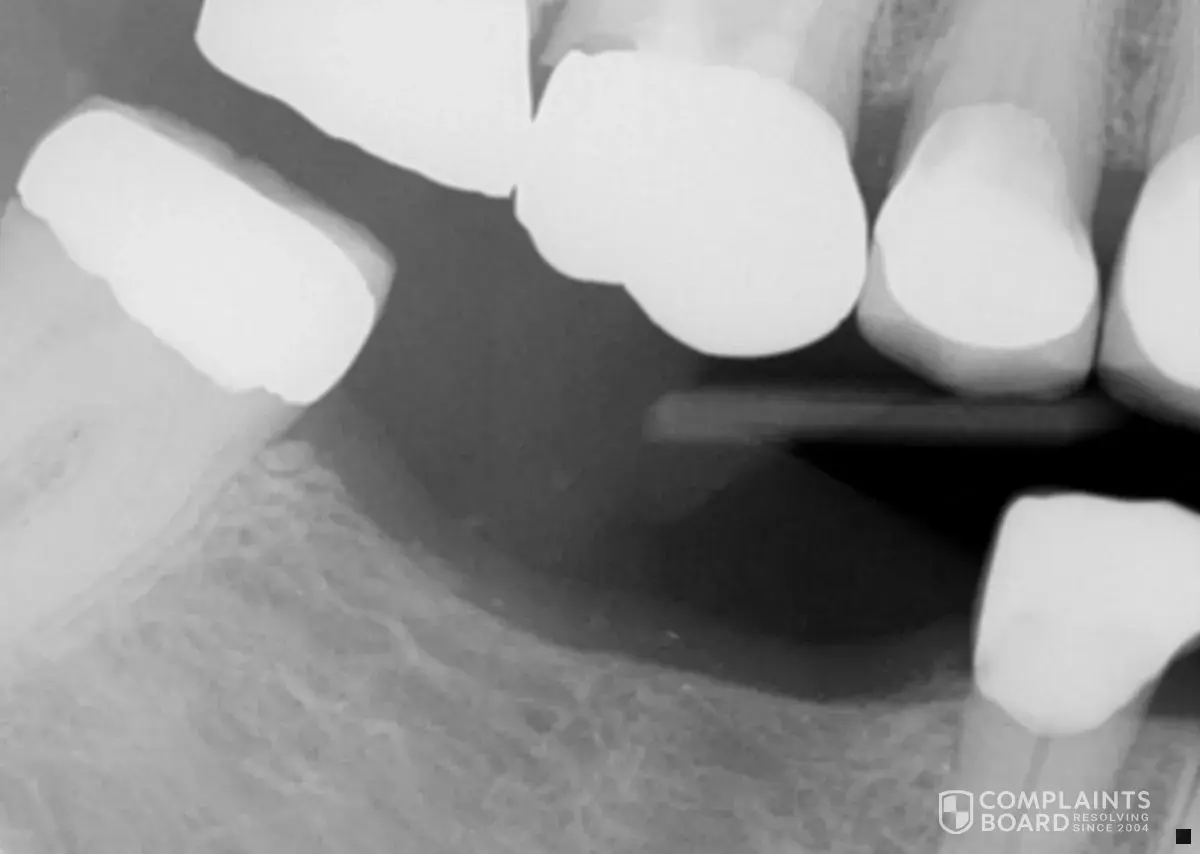

After receiving recommended endodontic treatment on tooth # 3 by B Taylor, DDS in Madison, WI on 1/11/2017, I was seen at Aspen Dental (Wausau Office) for placement of a crown on the named tooth. After a temporary crown was placed on tooth # 3, I received the permanent crown on 2/23/2017 for a cost of $863.36. On 08/6/2018, it was necessary to replace the crown on tooth # 3 as it was not fitted correctly as is obvious in the enclosed ex-ray, to the cost of $1200. Although, I realize that there is not a lifetime guarantee on a crown, a crown lasting for approximately 18 months is NOT normal.